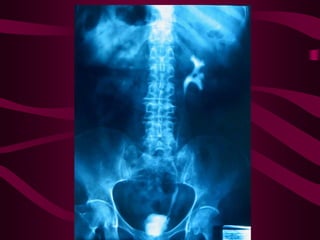

Este documento describe la tuberculosis genitourinaria. Afecta más a hombres que a mujeres. Se transmite principalmente a través de la infección pulmonar primaria y luego se disemina a través de la sangre a los riñones u otros órganos. Causa lesiones como granulomas y necrosis si no se controla, lo que puede provocar complicaciones como abscesos e insuficiencia renal. Se diagnostica mediante pruebas de orina y tratamiento con medicamentos durante varios meses.